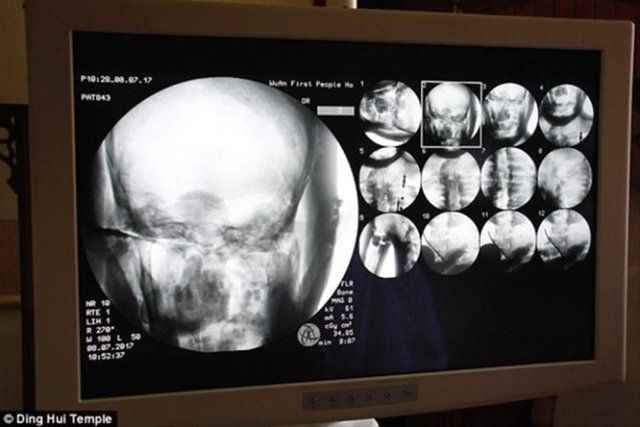

Tapınağın yönetimi, Ci Xian'ın cesedi için CT taramasını 8 Temmuz'da düzenledi. Doktorlar, Usta Ci Xian'ın, hala sağlıklı kemikleri ve bir beyni bulunduğunu söylediğinde, keşişler şok geçirdi.

Yapılan incelemede rahibin kemiklerinin hiç bozulmadığı ve beyninin zarar görmediği ortaya çıktı.

Üst çene, üst dişler, kaburga, omurga hepsi yerinde duruyor.